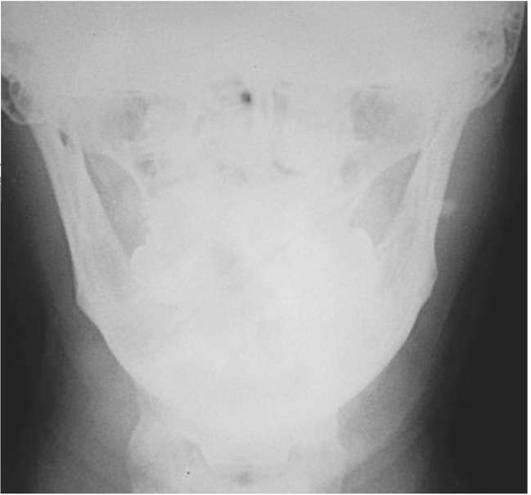

Диагностика. В распознавании слюннокаменной болезни имеет значение не только обнаружение камня, но и выявление причины камнеобразования. Анамнестический признак в виде слюнной колики в 99% случаев позволяет предположить наличие конкремента. На обзорных рентгенограммах рентгеноконтрастные камни хорошо визуализируются (рис. 6.11-6.13), на сиалограммах они видны в виде очага дефекта наполнения контрастного вещества. На эхосиалограммах камни видны по типу «звуковой дорожки». Особенно часто (более чем в 99%) камни выявляются на компьютерных томограммах.

Рис. 6.13. Рентгенограмма в проекции дна полости рта. В правой подъязычной области определяется камень